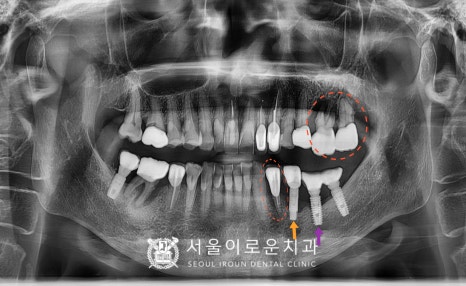

왼쪽 위아래 어금니의 불편감으로

서울이로운치과를

내원해 주신 환.자분의 사례를

통해 설명드리겠습니다!

오늘 소개해드릴 분은

70대 여성분으로

1년전부터

왼쪽 위아래 어금니가 흔들리고

씹.을 때 마다 아프시다며

전반적인 상.담을 원하셨는데요.

정밀한 검사를 위해

파노라마 사진을 촬영해 보았더니

✅ 불편감을 호소하셨던

빨간 동그라미 표시의

위턱 왼쪽 큰 어금니 두 개(#26,27)와

아래턱 왼쪽 첫 번째 작은 어금니(#34)는

치아 뿌리 끝까지 염증이 진행되어 있었으며

잇몸뼈가 녹아 동요도가 3도로

심하게 흔들리고 있고,

고름까지 나오고 있는 상태였는데요.

안타깝게도 이 경우에는

치아를 살려 쓸 수 없기 때문에

발치를 진행하기로 하였으며,

발치 후 염증조직을 깨끗하게 제거한 뒤

뼈이식을 동반한 임플란트 즉시 식립을

계획하였습니다.

더불어 타 치과에서 진행하셨던

아래턱 왼쪽 임플란트 주변으로는

임플란트 주위염이 관찰되었는데요.

✅ 특히 제일 앞쪽에 있는

주황색 화살표 표시의

아래턱 왼쪽 두 번째 작은 어금니(#35) 임플란트는

염증이 심한 상태라

임플란트 제거가 필요하였습니다.

✅ 보라색 화살표 표시의

아래턱 왼쪽 첫 번째 큰 어금니(#36)의 임플란트도

1/3 정도의 뼈 흡수 소견이 보이나

환.자분께서 유지관리하시길 원하시어

염증 제거 후 유지 관리하기로 했습니다.